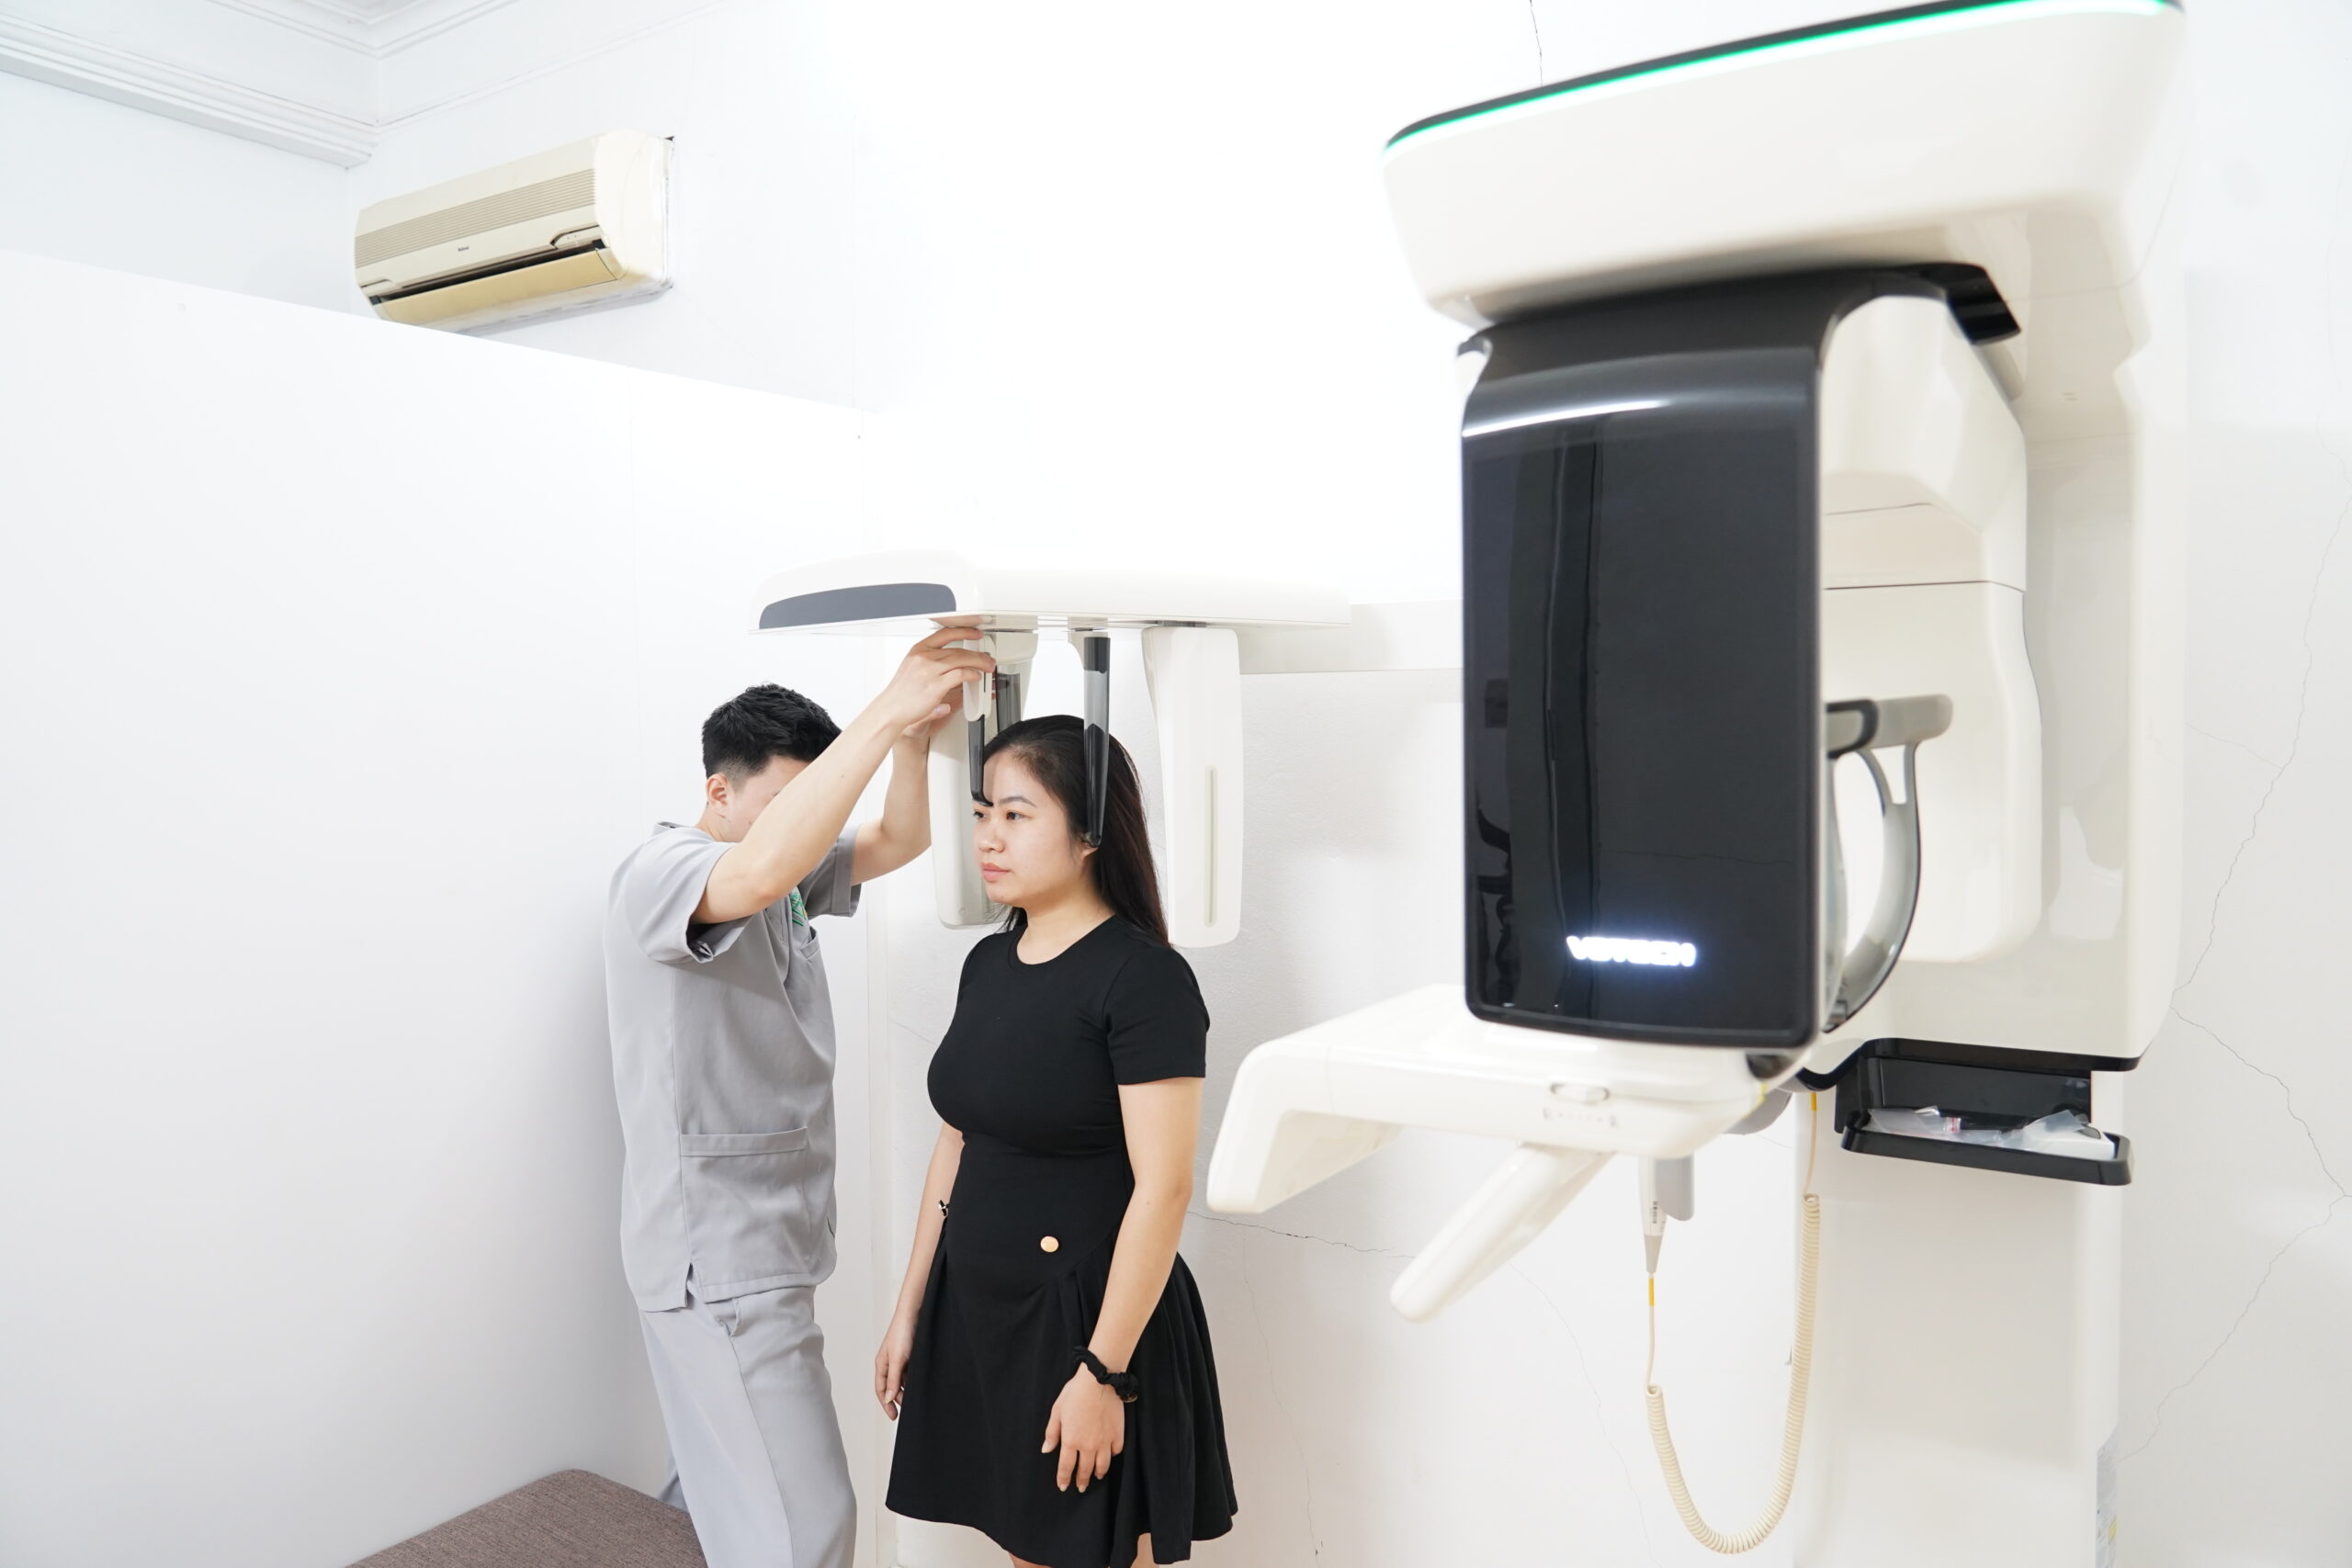

CÔNG NGHỆ SỐ TIÊN TIẾN TRONG ĐIỀU TRỊ:

CÔNG NGHỆ SỐ TIÊN TIẾN TRONG ĐIỀU TRỊ

Máy chụp hình 3D Itero

Máy chụp hình 3D Itero

Máy chụp hình 3D Itero

Máy chụp hình 3D Itero

CÔNG NGHỆ SỐ TIÊN TIẾN TRONG ĐIỀU TRỊ 2

QUY TRÌNH ĐIỀU TRỊ LOẠN NĂNG KHỚP THÁI DƯƠNG HÀM TẠI NHA KHOA TRẺ